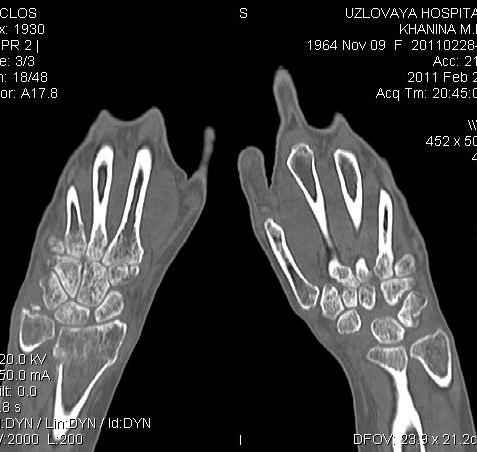

Уважаемые коллеги.Прошу обсудить случай лечения перелома дистального метаэпифиза лучевой кости. Ситуация скандальная и крайне неблагоприятная. Больная с патологической обстоятельностью мышления, склонностью к сутяжничеству, патологическими умозаключениями, не поддающимися коррекции (см. психиатрию, правда офиц. диагноза нет). В данном случае есть ряд ошибок с нашей стороны, прежде всего в отношении качества ведения документации (за что получил административное взыскание, по делом мне дураку). В остальном- придерживались в лечении подхода классический советской школы. Так как умную операцию…… сами знаете… 15.12- перелом луча в Москве. Там же репозиция, гипс. Дальнейшее лечение у нас в ЦРБ. 20.12.- вторичное смещение в гипсе21.12- под внутривенным наркозом- репозиция, гипсовая лонгета. Дальше начинается самое интересное. После репозиции больная заявила, что я (репозицию делал я) порвал ей все связки в суставе, посинел у нее 5 палец, якобы я за него тянул и т. д. На самом деле на 2 сутки после репозиции рука немного отекла и было незначительное сдавление гипсом, который был ослаблен. Дальнейшее лечение консервативное. Через 6 недель- гипс снят, назначено ЛФК. Пациентка крайне недовольна. Говорит, что на снимке у нее выступает кость, я ей сломал руку и.т.д. В общем началось. Пациентка прочитала в интернете наверное все, что есть по данной травме.По заключениями рентгенологов и консультанта из КДЦ областной больницы - стояние отломков допустимое. Объективно говоря- снижена высота лучевой кости, диастаз лучелоктевого сочленения, и не сросся шиловидный отросток. однако на РКТ при сравнении с другой стороной- разница незначительная. Дальше в одной из больниц нашей области и одной из больниц Москвы (вроде бы КГБ 53) врачи сказали, что репозиция сделана плохо. Нужна операция (восстановить длину лучевой кости), даже один из них предложил РЕДРЕССАЦИЮ (хи-хи) с наложением аппарата Илизарова. Что это для данной больной- радость неописанная. (см. описание психического статуса). Ничем другим, кроме зарабатывания дешевого авторитета объяснить данный факт не могу.Кстати, у больной еще нейропатия локтевого нерва.Для разрешения конфликта больная направлена на консультацию в ЦИТО на 03.03.11.

Теперь вопросы: 1.Прошу объективно оценить качество нашей репозиции на момент 21.12. (неужели так плохо?). Что на снимках при снятии гипса- сам вижу. 2. сравнить снимки РКТ (с двух сторон)- так ли велико укорочение лучевой кости и лучелоктевой диастаз. 3. Ваши мнения, в отношении целесообразности оперативного лечения учитывая ВСЕ вышеизложенное. 4. На всякий случай для суда- мог ли я тракцией в 2- 3 кг за 1 и 2 пальцы под внутривенным наркозом неправильно вколотить отломки и травмировать локтевой нерв. Кстати, в США если врач пациенту говорит, что его плохо лечили- то этого врача лишают лицензии. У нас наооборот- обгадить другого милое дело. И это процветает. От себя же могу сказать, что никто в нашем отделении так не поступает. Коллеги, будьте осторожны в своих высказываниях. От осложнений и ошибок никто не застрахован. А в данном случае многое будет зависеть от заключения консультантов поликлиники ЦИТО, куда больная направлена областным травматологом на 03.03 для решения вопроса о дальнейшей тактики лечения. С уважением ко всему травматологическому сообществу Дедок Михаил.

1. РЕПОЗИЦИЯ сделана качественно(ОСНОВНЫЕ 2 УГЛА ВЫСТАВЛЕНЫ ПРАВИЛЬНО ) , но перелом нестабильный и склонен к втор смещению . Поэтому мы стараемся все переломы со смещением фиксировать 3-МЯ спицами по GRIN методике .

2. По сравнению и без ! втор смещение незначительное.НЕТ НИКАКОЙ ,,локтевой косорукости,,маделунгов . но имеется смещение совести у врачей КГБ 35--НЕТ ЗДОРОВЫХ, есть только недообследованные ! Этому смещению аппарат внешней фиксации не поможет .Психопаткам в менопаузе да весной только этого и надо чуть толкнули и поехало .